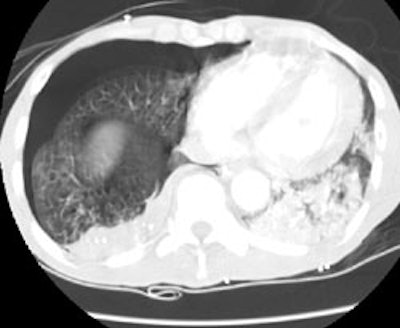

Computed Tomography: On CT the pleural thickening or calcification is clearly identified. Thickened lung markings and vessels swirl into the lesion which abuts the pleural surface ("comet tail sign"- central bronchovascular pedicle)- however, this finding may be absent in up to 8% of cases. Curvilinear air bronchograms are often visible within round atelectasis. The lesion is very commonly based or tethered by a strand to a thickened pleural surface. Pericicatril emphysema may also be seen. Volume loss within the affected lung is also common- often characterized by displacement of the fissure bounding the affected lobe. Calcification may also be found within areas of round atelectasis (up to 25% of cases)- possibly secondary to engulfment of a granuloma within the atelectatic lung, or invagination of a calcified pleural plaque. The lesion will enhance homogeneously after the administration of I.V. contrast (up to nearly 90% of cases). Inhomogeneous enhancement is atypical for rounded atelectasis [12].

Despite the ability of computed tomography to accurately identify features which are often associated with round atelectasis, it should be remembered, that the findings described above are not necessarily completely diagnostic for this entity. Other lesions can mimic these findings and rarely lung cancer can co-exist in an area of round atelectasis [12].

Round atelectasis on PET FDG imaging: The images below demonstrate the typical CT and FDG PET findings in round atelectasis. On CT, there are thickened lung markings and vessels which swirl into the lesion that abuts an area of pleural thickening. Note the lack of metabolic activity in round atelectasis on PET imaging. |